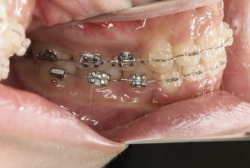

今回は「歯並びの凸凹を治したい」という主訴で来院したケースです。診断の結果、「成長発育期の叢生」と判明しました。叢生とは歯並びの凸凹のことですが、この方の場合は上顎が少々重症で、上の犬歯が外側へ飛び出し、いわゆる「八重歯」という状態でした。凸凹の解消のためには永久歯を抜歯して隙間を作って残った歯をきれいに配列する方法(抜歯法)と、歯列を拡大して配列する方法(非抜歯法)の2種類があります。歯列の拡大にはさらに2つの方法が有り、横方向へ拡大する場合と、臼歯を後方に移動させて拡大する方法があります。今回の症例のようなケースでは、横方向へ拡大してもあまり効果的ではなく、後方への移動が最適です。上の臼歯を後方へ移動させるために、今回はヘッドギヤという取り外し式の装置を、夜寝る時に半年ほど使用していただきました。

注意点としてここでお伝えしたいのは、矯正専門医ではない歯科医院で、いわゆる「床矯正」という方法を行うと、たいてい横方向の拡大になってしまいます。無駄に横方向の拡大をするとかえって症状を悪化させたり、何の効果もないことになってしまいます。一見簡単そうな矯正に見えたとしても、しかるべき矯正専門医に診断してもらうことをおすすめします。

この方の場合、治療期間はヘッドギアを6ヶ月、マルチブラケット法を7ヶ月でした。治療後は凸凹が改善しただけでなく唇の審美性が大幅に改善しました。もちろん噛み合わせ的にも正しい状態が確立しています。